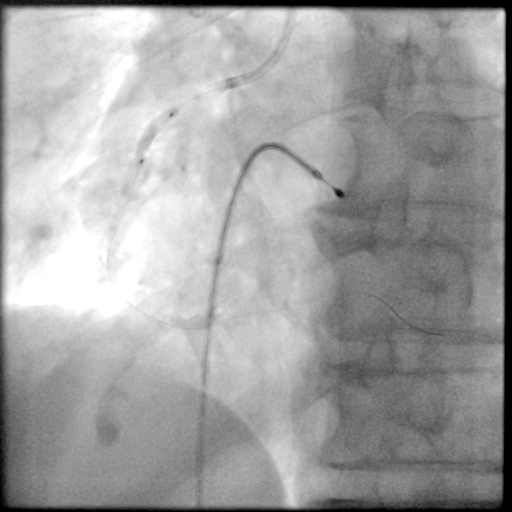

PCI过程-冠状动脉旋切(轨道旋磨)术-1

IVUS导管无法通过,微导管辅助下,将旋磨导丝置于RCA远端,应用1.0mm磨头以13万转反复旋磨钙化病变处(每次15秒,磨头推进速度不超过10 mm/s)

PCI过程-冠状动脉旋切(轨道旋磨)术-2

微导管辅助下,将旋磨导丝置于RCA远端,应用1.0mm磨头以13万转反复旋磨钙化病变处(每次15秒,磨头推进速度不超过10 mm/s)

PCI过程-冠状动脉旋切(轨道旋磨)术-3

共计旋切170秒,术后,狭窄较前减轻